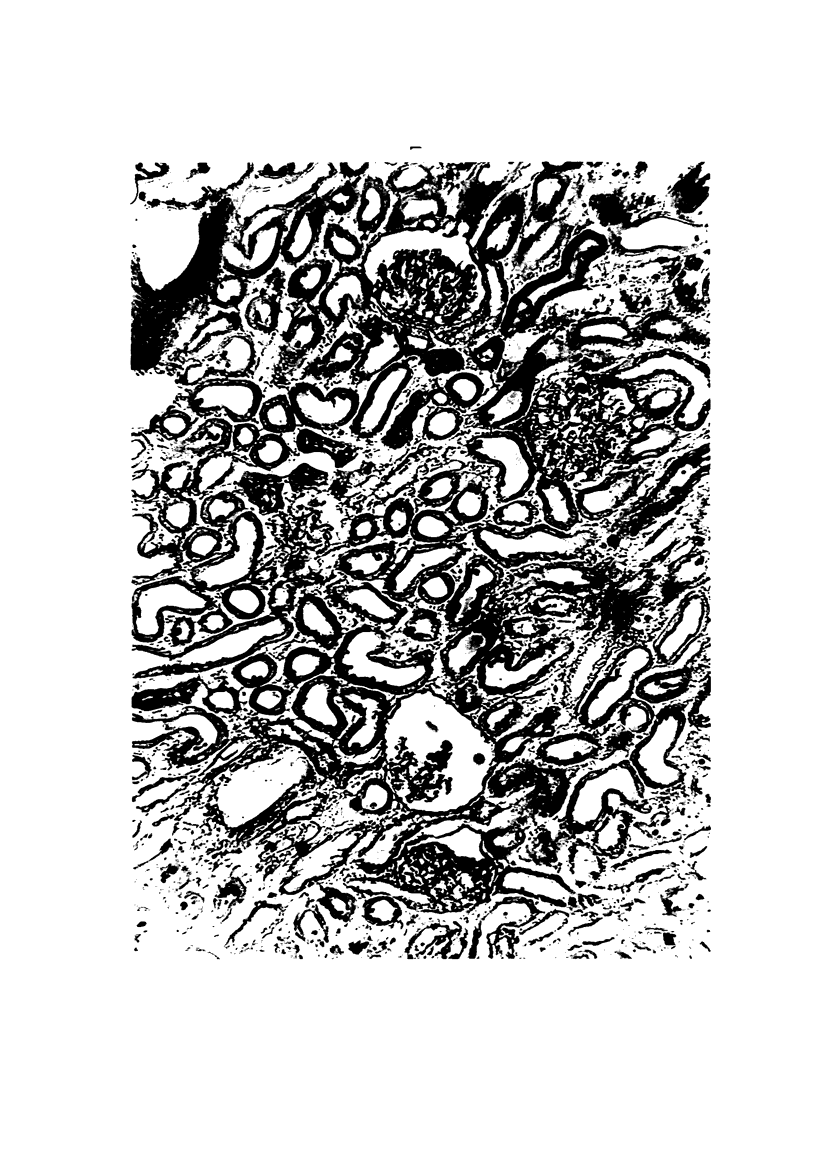

The qualitative Hanssen technic was used to study the mechanism of anuria produced in rabbits by mercury poisoning. Twenty-four to 30 hours after intravenous injection of a low dose of HgCl2, the animals were almost completely anuric. Sodium ferrocyanide injected intravenously was visualized as Prussian blue in essentially all glomeruli in anuric kidneys, and the amount of the dye in the glomerular tufts was almost the same as in control kidneys. Thus there was no evidence for a severe reduction in glomerular capillary blood flow. Besides, the distribution of Prussian blue in tubular lumina indicated that the anuria occurred in the presence of a significant glomerular filtration. Tubular walls of the anuric kidneys showed an abnormally increased permeability to sodium ferrocyanide. These findings suggested that the anuria during this stage was caused more by tubular leakage than by intrarenal vasoconstriction and subsequent cessation of glomerular filtration.

Images in this article